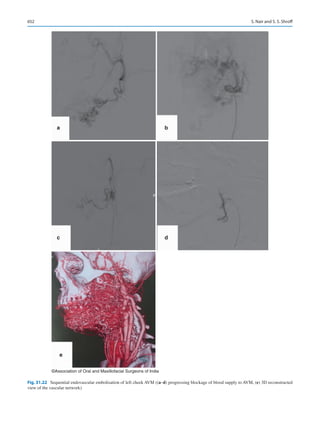

icine man for their healthcare. Direct to consumer marketing